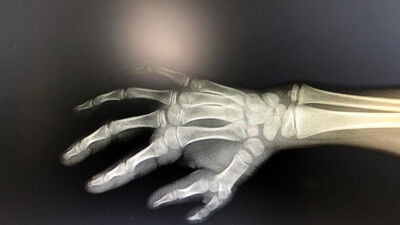

Gümüşhane'de 12 yaşındaki çocuğun doğuştan fazla olan bir parmağı, başarılı operasyonla alındı. AA'nın haberine göre; Şiran ilçesinde yaşayan ve sağ elinde 6 parmak olan A.Ç, Gümüşhane Devlet Hastanesine başvurdu. Plastik Cerrahi Uzmanı Opr. Dr. Sultan Yalçın tarafından muayene edilen çocuğun ameliyatına karar verildi.

Başarılı operasyonla çift başparmaktan biri alınan A.Ç, artık sağ elini de sağlıklı şekilde kullanabilecek.

Opr. Dr. Yalçın, 12 yaşındaki çocuğun doğumsal baş parmak fazlalığı şikayetiyle kendisine başvurduğunu söyledi.

Muayenenin ardından eldeki fazla parmağın alınması için operasyon planladıklarını anlatan Yalçın, şöyle devam etti: "Bu binde bir görülen bir sorundur. Buna çok parmak diyoruz. Genellikle bu tür durumlar bebeklik çağında ameliyat edilerek çözüme kavuşturulur ancak bu hastamız için bu işlemin yapılması geciktirilmişti. Bize geldiklerinde hızlıca operasyonu planladık. Gayet başarılı bir operasyonla sağ elindeki parmak fazlalığını giderdik. Artık elini daha iyi kullanabilecek. Uzun kıyafetlerle elini saklamak zorunda kalmayacak. Ona yardımcı olabildiğim için mutluyum."